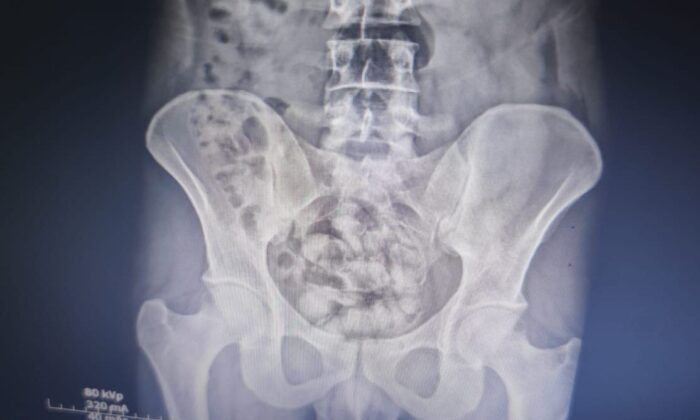

Van polisi ve MİT’in ortak düzenlediği diğer operasyonda ise İran uyruklu bir şüphelinin midesinde uyuşturucu olduğu belirlendi. İran uyruklu S.Y.’nin üzerinde yapılan aramada 23 gram metamfetamin bulunurken, şahsın iç beden muayenesinde ise midesinde 25 kapsül şeklinde 351 gram metamfetamin olduğu tespit edildi. İran uyruklu şahıs gözaltına alındı.